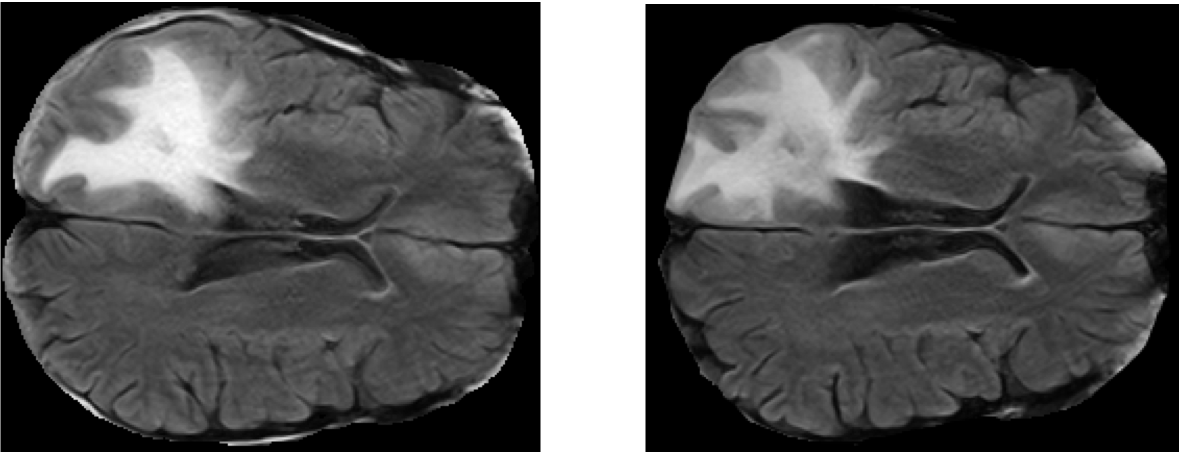

In order to make our results comparable, the analysis 2 and 3 were executed by using a public freely available dataset accessible via The Cancer Imaging Archive (TCIA) Clark et al. (2013). In details, the dataset includes DICOM files of 20 subjects from different sites with primary newly diagnosed glioblastoma who were treated with surgery and standard concomitant chemo-radiation therapy (CRT) followed by adjuvant chemotherapy. The sequences are T1-weighted (pre and post-contrast agent), FLAIR, T2-weighted, ADC, normalized cerebral blood flow, normalized relative cerebral blood volume, standardized relative cerebral blood volume, and tumour masks (i.e., ROIs) Schmainda and Prah (2018); Ellingson et al. (2009). Fig. 1 shows two among the 2D slices contained in the dataset and extracted from FLAIR. Each patient is described by two MRI exams: within 90 days following CRT completion and at progression. At the best of our knowledge, in this paper the dataset is used for the first time for ML experiments Schmainda et al. (2018). The following preprocessing steps were performed before running the analysis:

The dataset contains for each patient two MRI exams: the exams were recorded within 90 days following CRT completion and at progression, for now on ”pre" and ”post". For each patient the topological features (i.e. Euler characteristics, persistent entropy at H0 and H1 and generator entropy) were computed on the 2D slices of FLAIR. Welch’s t-test is used for comparing the mean of the topological descriptor computed over the ”pre" and ”post" set of images. Fig.:3 depicts of two FLAIR slices extracted for the same patients within 90 days following chemo-radiation therapy (CRT) completion and at progression.